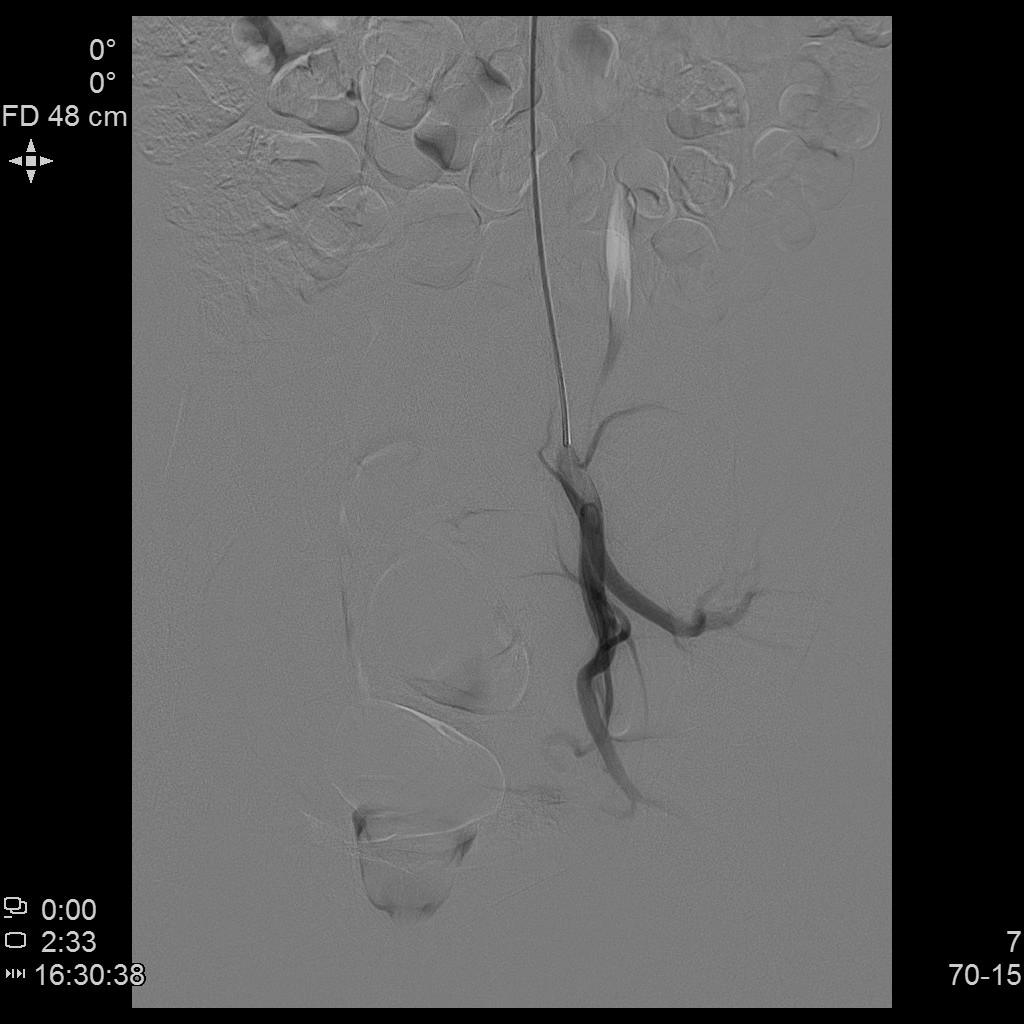

- 微导管进一步超选插管右侧子宫动脉主干造影确认位置。

右侧子宫动脉造影

- 微导管进一步超选插管左侧子宫动脉主干造影确认位置。

左侧子宫动脉造影